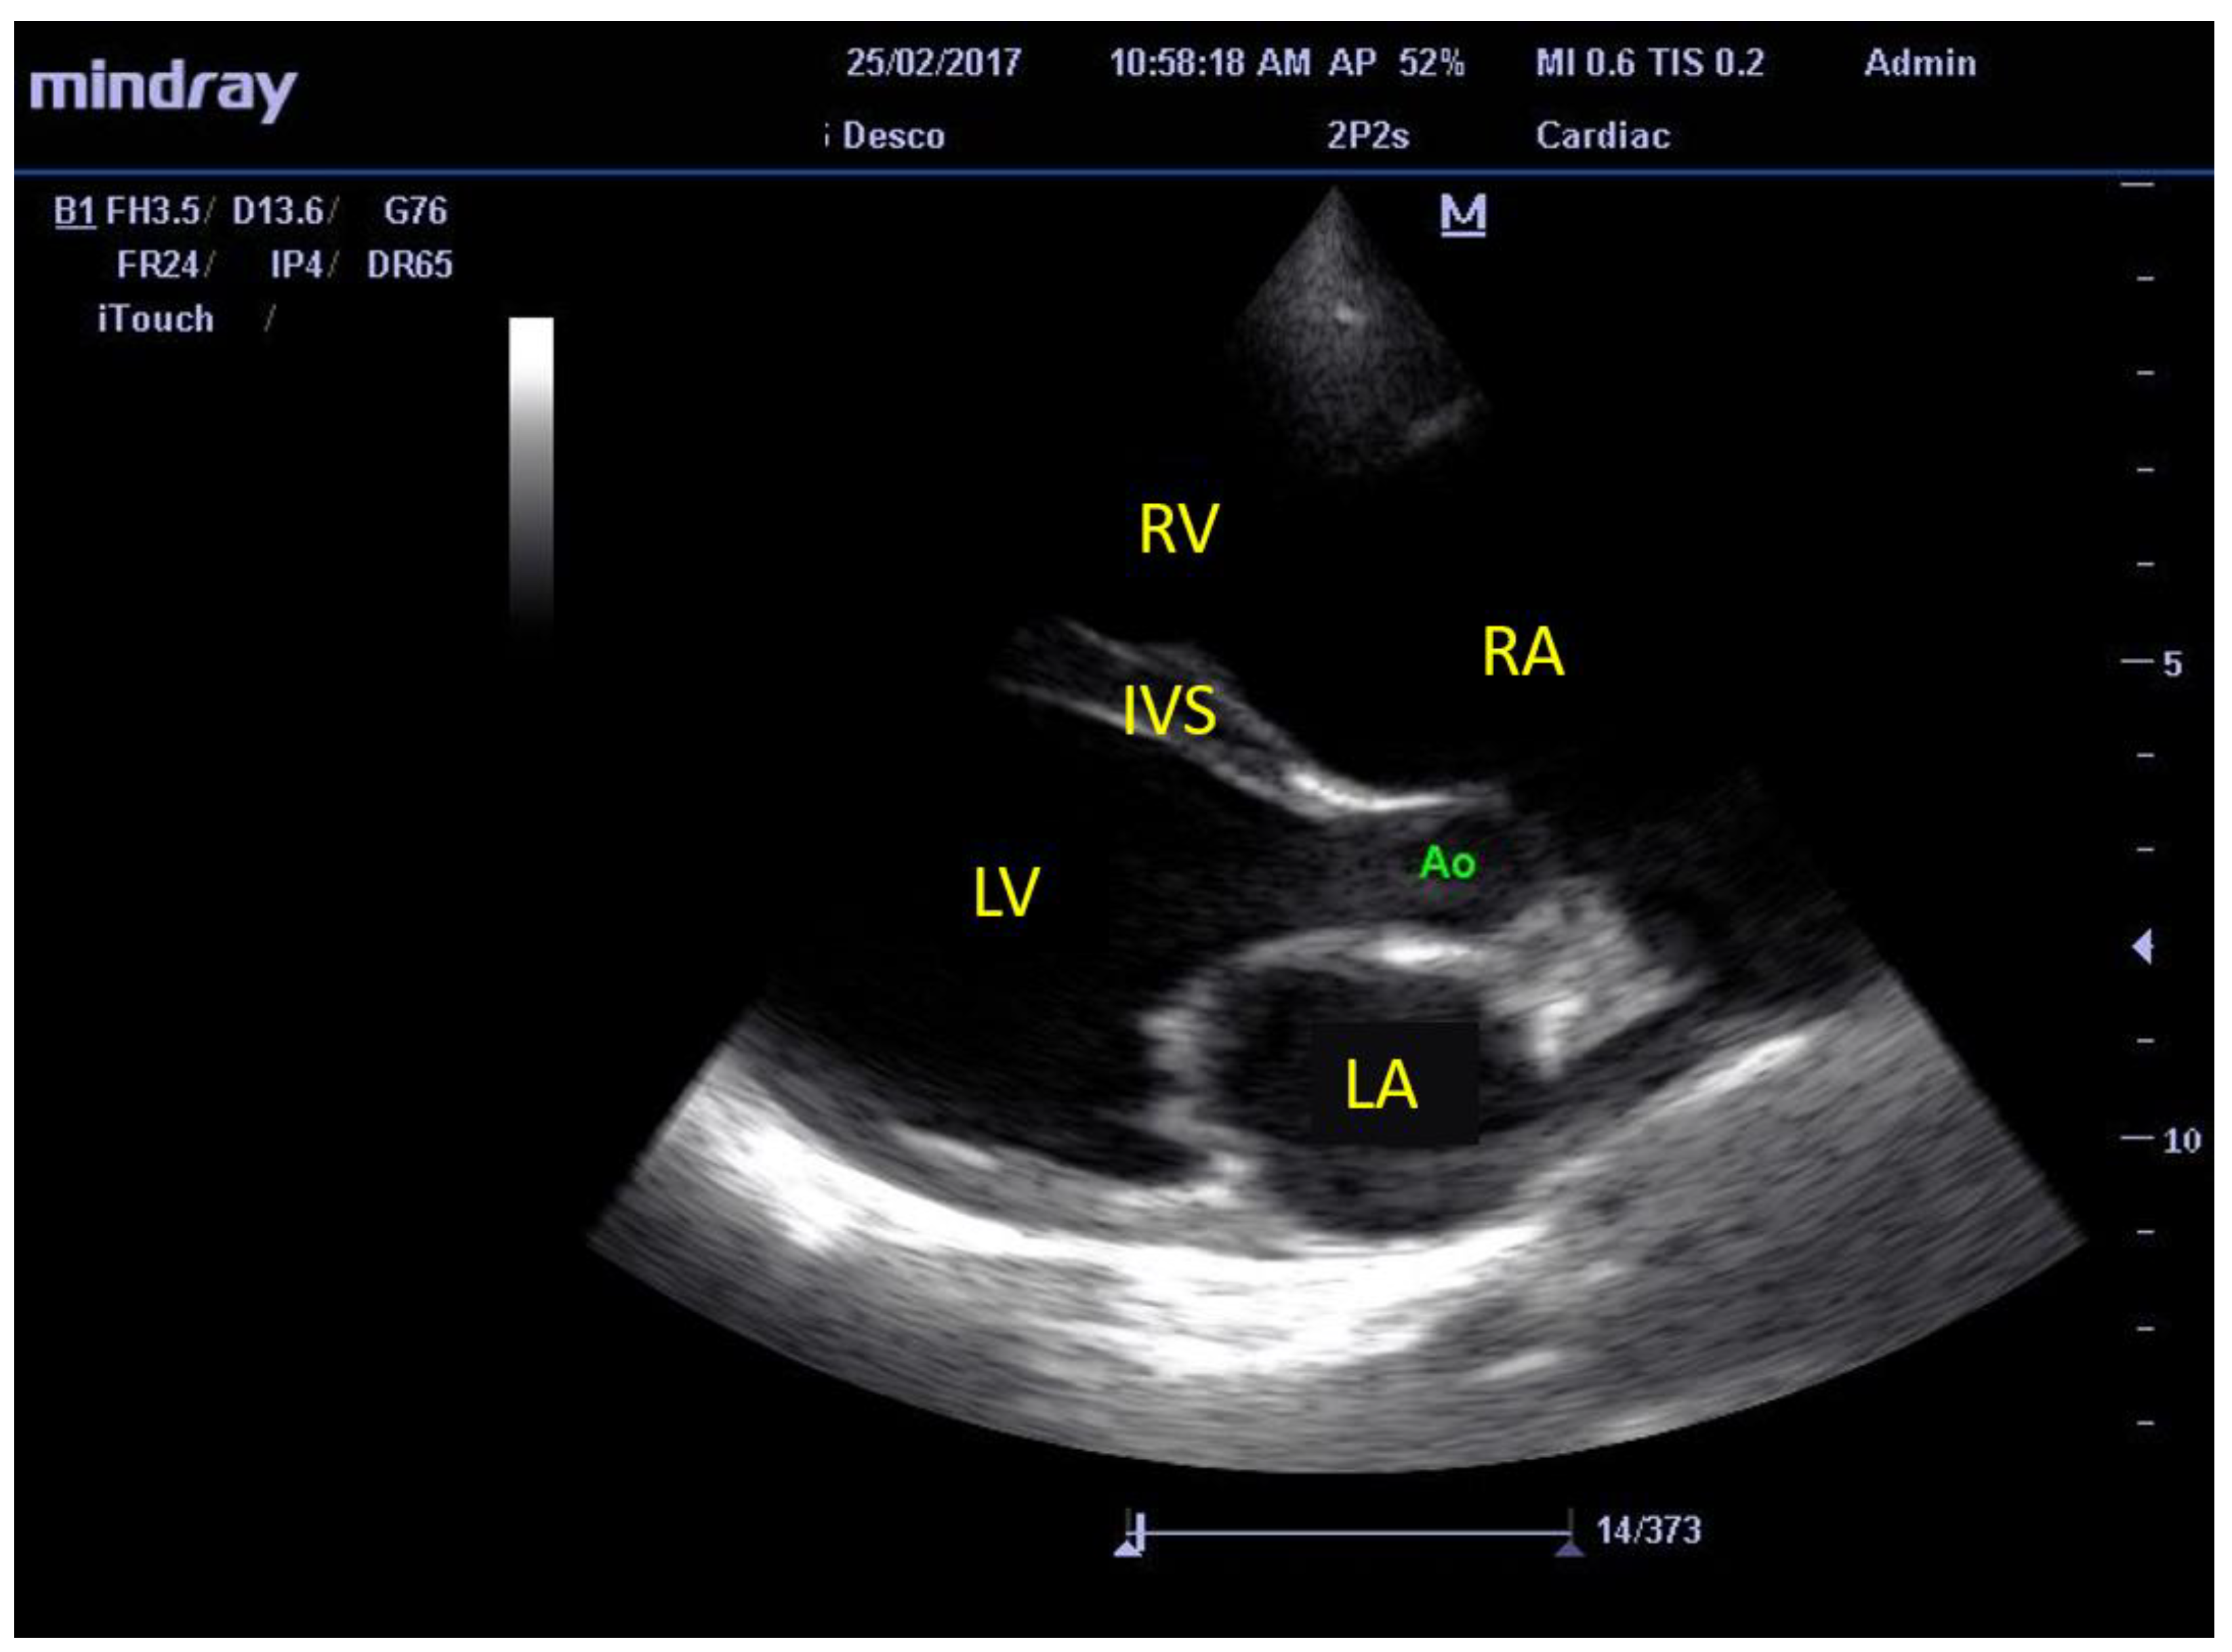

2.7. Echocardiographic Evaluation of Cardiac Structures and Function

3.2. Echocardiographic Findings

3.3. M-Mode Ultrasonographic Findings